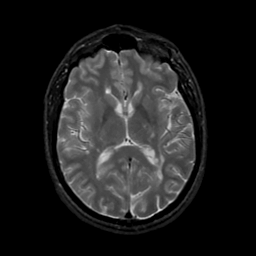

MR Study #20 October 6, 1991 -- Slice #27

[Home][Help][Clinical][Tour 1][Tour 2] Slice 27